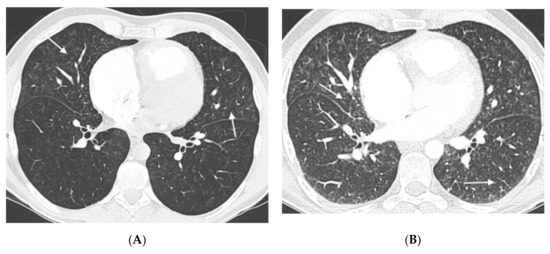

Figure 2.

Forty-six-year-old man referred from another center with a diagnosis of idiopathic PAH. (A) MDCT on admission: parenchymal involvement with faint centrilobular nodules in ground glass (arrows); (B) MDCT after initiation of vasodilator treatment. Radiological worsening with increased ground glass involvement and the appearance of septal lines (arrows) in relation to pulmonary edema. The patient was finally diagnosed with hereditary PVOD.